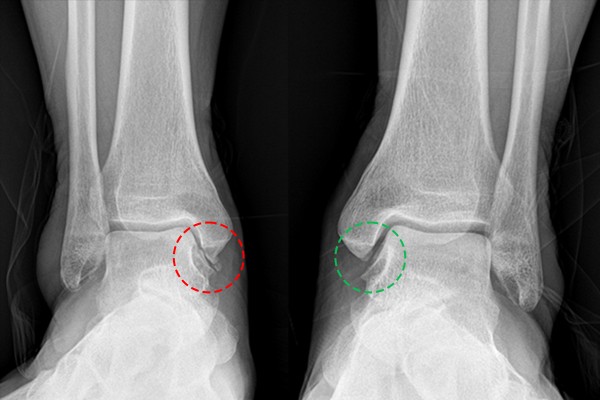

촬영한 발목 X-RAY에서 발목 관절의 공간이 확인되는 좌측 발목에 비해, 우측 발목 관절의 경우 공간이 없는 것을 확인하여 우측 발목 관절염 (Takakura stage 3B)(OA ankel Rt.(Takakura stage IIIB))을 진단하였습니다.

수술 전/후 X-RAY를 비교해보면 더욱 확실하게 알 수 있습니다.